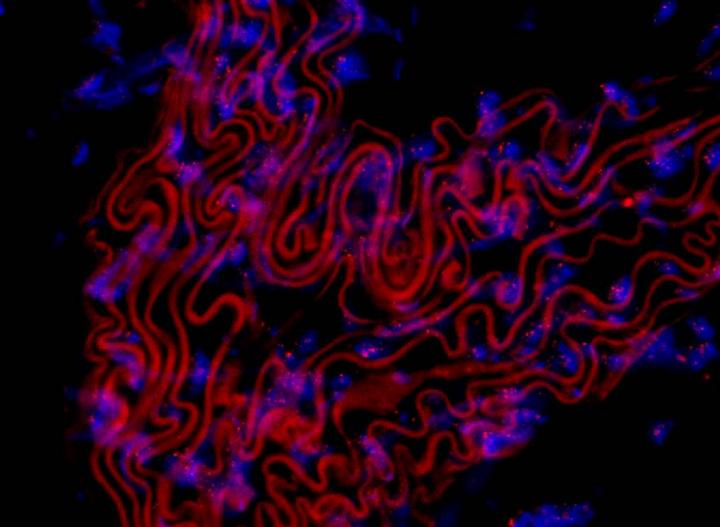

image: Microcopic image of thin sections of a thoracic mouse aorta exposed to a fluorescent probe to stain telomeres. Nuclei of cells are stained blue and telomeres are shown by red dots within nuclei. The fluorescence intensity correlates with telomere length. Red curved lines are from elastin auto-fluorescence.

PD Dr. Christian Werner, University Clinic of the Saarland, Homburg, Germany, and the European Heart Journal.